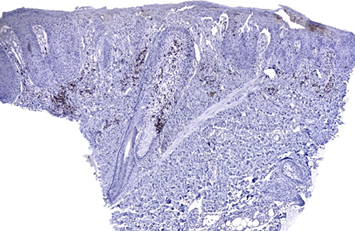

Figure

4.

Moderately strong perinuclear and cluster CD30+ expression

Courtesy Dra.

Johanna Brito – LunaPiel